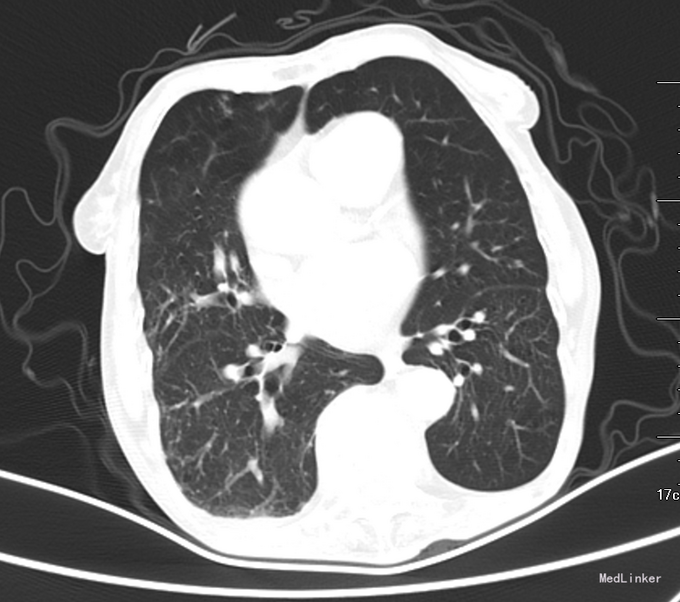

查体:T37.2℃,P72次/分,R18次/分,BP145/77mmHg。神清语明,平车推入病房,查体合作。全身皮肤及巩膜无黄染,睑结膜无苍白。颈静脉无充盈,未触及锁骨上淋巴结,听诊双肺呼吸音清,未闻及明显干湿罗音。心音纯,律齐,剑突下可见心尖搏动,各瓣膜区未闻及病理性杂音。腹软,肝脾肋下未触及,腹部无压痛及反跳痛,双侧输尿管区无压痛,肝区肾区无叩痛,移动性浊音阴性,双下肢无水肿。腱反射正常,病理反射未引出。 辅助检查:2015-07市中心医院胸部CT:双肺气肿,考虑双肺感染性病变,双侧胸腔少量积液,冠状动脉钙化。:CRP:15.6mg/L;结核抗体测定:结核抗体 弱阳性;血清离子:钾 3.85mmol/L;钠 145.5mmol/L;氯 108.2mmol/L;钙 2.14mmol/L;血常规+BG:白细胞计数 3.910^9/L;中性粒细胞百分比 56.4%;血小板计数 21910^9/L; T-SPOT:阳性。